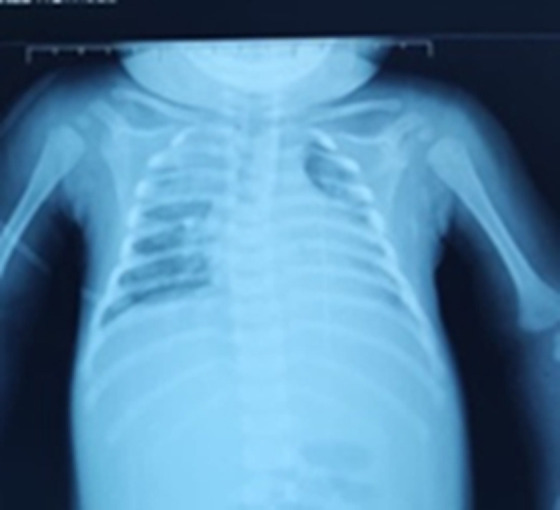

我们正在处理一个女婴病例,她有脑静脉血栓,显示继发性免疫缺陷,由于人类免疫缺陷病毒感染。在用低分子肝素(LMWH)进行抗凝治疗后,发现她患有严重的血小板减少症,这表明血小板减少症是由肝素的自身免疫来源引起的。在发展中国家,确诊手段并不总是可用,因此很难确定严重血小板减少症是由于艾滋病毒感染、败血症还是肝素所致。因此,治疗决定是困难的,因为停止抗凝可能导致脑血栓扩展。

We are dealing with a female infant case who had a cerebral venous thrombosis, revealing a secondary immunodeficiency, owing to a human immunodeficiency virus infection. After anticoagulant treatment with low-molecular-weight heparin (LMWH), it came to light that she had a severe thrombocytopenia, suggesting a thrombocytopenia induced by an auto-immune origin of heparin. Within a developing country in which means of confirmation are not always available, it was difficult to identify whether severe thrombocytopenia was owing to HIV infection, sepsis, or heparin. The therapeutic decision was therefore difficult, because stopping anticoagulation can lead to a cerebral thrombosis extension.